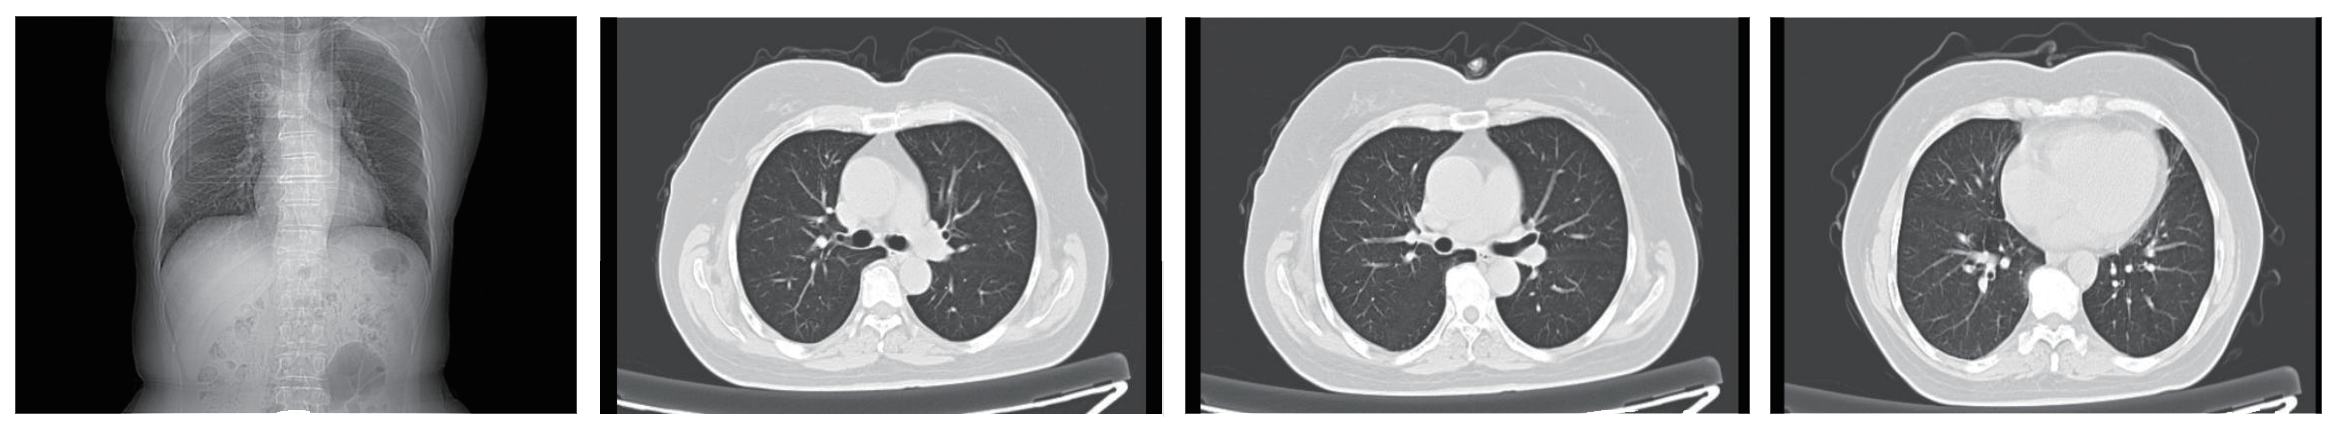

Chest